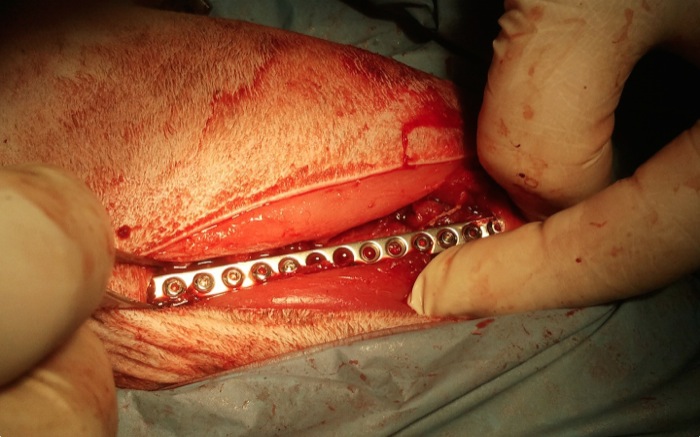

Se colocan, con abordajes que se alienan desde la piel el fémur y el ileon, las placas correspondientes. El fémur presenta una amplia zona diafisaria media solo con la cortical posterior intacta lo que impide la colocación de tornillos en mas de un tercio de la longitud de la placa.

El ileon del mismo lado queda bien posicionado y aunque se valora una fijación adicional mediante 2 tornillos se descarta ante la aparente estabilidad. No se quiere prolongar el tiempo quirúrgico ante el estado aún delicado del paciente, también por ello se pospone la siguiente cirugía.